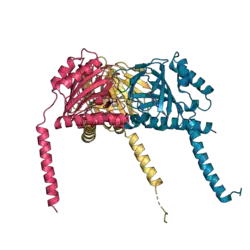

The mammalian σ1 receptor is an integral membrane protein with 223 amino acids.[16] It shows no homology to other mammalian proteins but strikingly shares 30% sequence identity and 69% similarity with the ERG2 gene product of yeast, which is a C8-C7 sterol isomerase in the ergosterol biosynthetic pathway. Hydropathy analysis of the σ1 receptor indicates three hydrophobic regions.[17] A crystal structure of the σ1 receptor was published in 2016.[18]